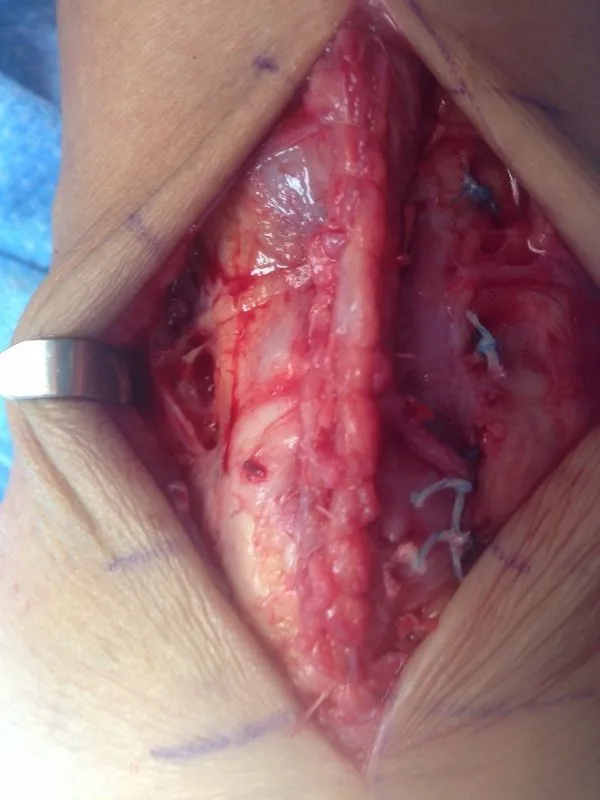

Below, Intraop Pics of intrasubstance tear of Peroneus Longus with excision of low lying muscle belly, tear and repair

Below, Intraop Pics of intrasubstance tear of peroneus longus with repair

Below, Intraop pics of low lying muscle belly of peroneus brevis

Below, Pic of low lying muscle belly resection of the peroneus brevis which causes pain due to congestion.